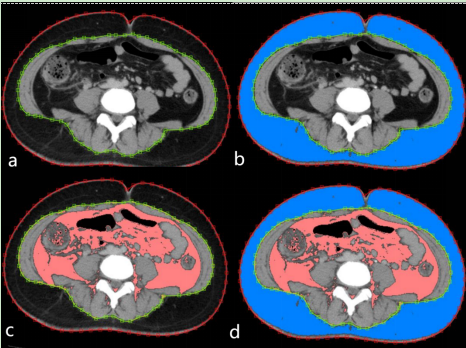

(五)胰腺炎和代謝性肝病CT/MRI檢查,針對急性胰腺炎的磁共振成像檢查能提供胰腺內(nèi)外、腹膜后間隙的病理變化圖像,為胰腺炎的嚴(yán)重程度早期評估、局部并發(fā)癥評估提供重要參考依據(jù)。肥胖癥相關(guān)的代謝性肝病磁共振成像檢查能無創(chuàng)性提供肝臟脂肪含量的情況,以及評估人體的皮下、內(nèi)臟脂肪和肌肉面積/體積相關(guān)信息,為減重手術(shù)的開展和術(shù)后影像學(xué)隨訪提供循證依據(jù)。

圖片

胰腺炎和代謝性肝病CT/MRI檢查